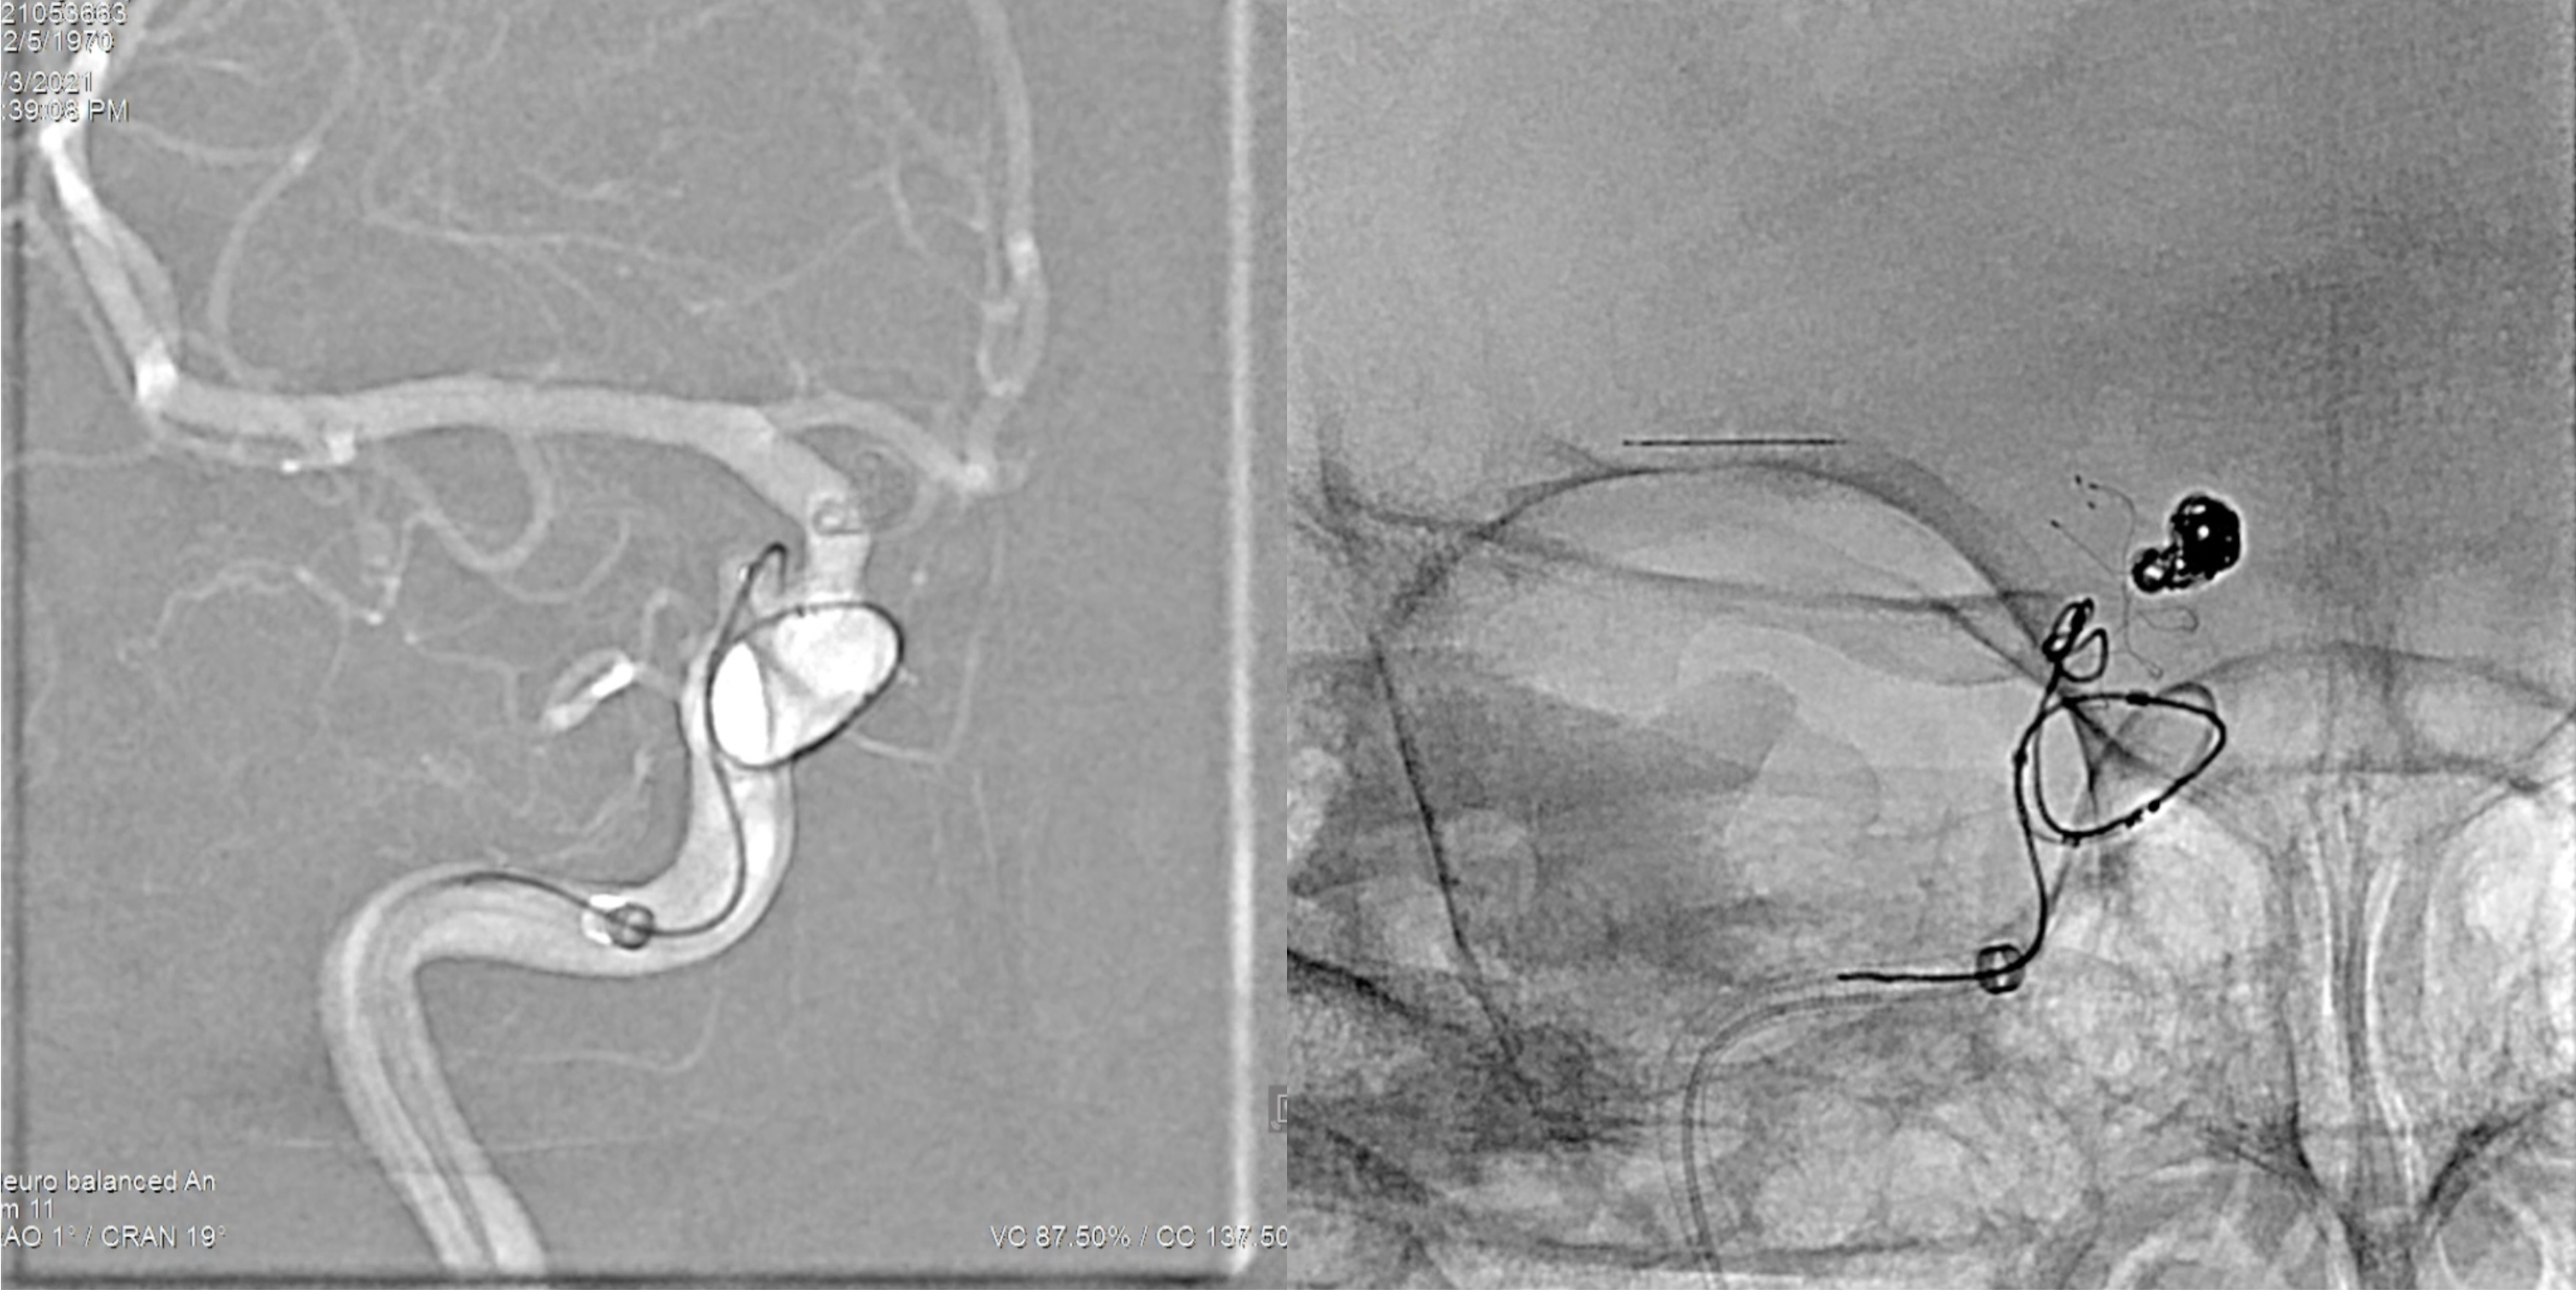

7F长鞘+6F Navien建立左侧颈内动脉栓塞通路后,栓塞微导管超选进入动脉瘤瘤腔内。

行单纯栓塞,工作位造影及蒙片显示:动脉瘤栓塞完全!撤除栓塞导管。

术后左侧颈内动脉正侧位造影显示:动脉瘤栓塞完全!各级血管通畅。撤除通路系统。

将7F长鞘+6F Navien再次超选至右侧颈内动脉建立通路系统后,Headway-21支架导管及Echelon-10栓塞微导管超选到位!

选择Lvis 3.5*20mm支架半释放辅助下先行后交通动脉瘤栓塞,动脉瘤栓塞满意后,撤除栓塞微导管。

将Echelon-10微导管超选入眼动脉段动脉瘤瘤腔内,行首枚弹簧圈栓塞。

造影确认动脉瘤栓塞完全后撤除各级栓塞导管。

术后右侧颈内动脉正侧位造影:动脉瘤栓塞完全!

术后三维旋转造影:动脉瘤栓塞完全!